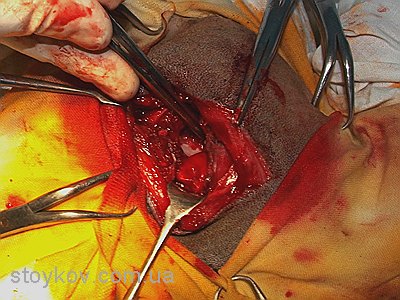

Саме тому у більшості випадків вибір залишається за хірургічним лікуванням. Мета хірургічного лікування – зменшення болю, але зважаючи на невеликий розмір тварини, функція прооперованої кінцівки залишається задовільною. Для проведення операції потрібно використовувати остеотом або осциляторну пилку. Використання дротяної пилки не бажано тому, що у такому випадку зріз буде проведено у найвужчому місці шийки, тобто посередині, а потрібно відсікати всю шийку повністю. Не дивлячись на удавану простоту операції дуже важливо провести правильну лінію зрізу шийки стегна і максимально зберегти капсулу суглоба. Після відсікання шийки стегна потрібно ретельно зашити капсулу суглоба. Інколи, для збільшення прошарку м’яких тканин між стегновою кісткою і тазом, використовують техніку м’язового клаптику. Якщо така операція проводиться у собак до 7 кг маси тіла то інтерпозиція частини двоголового мускулу не обов’язкова.

техніка оперативного втручання